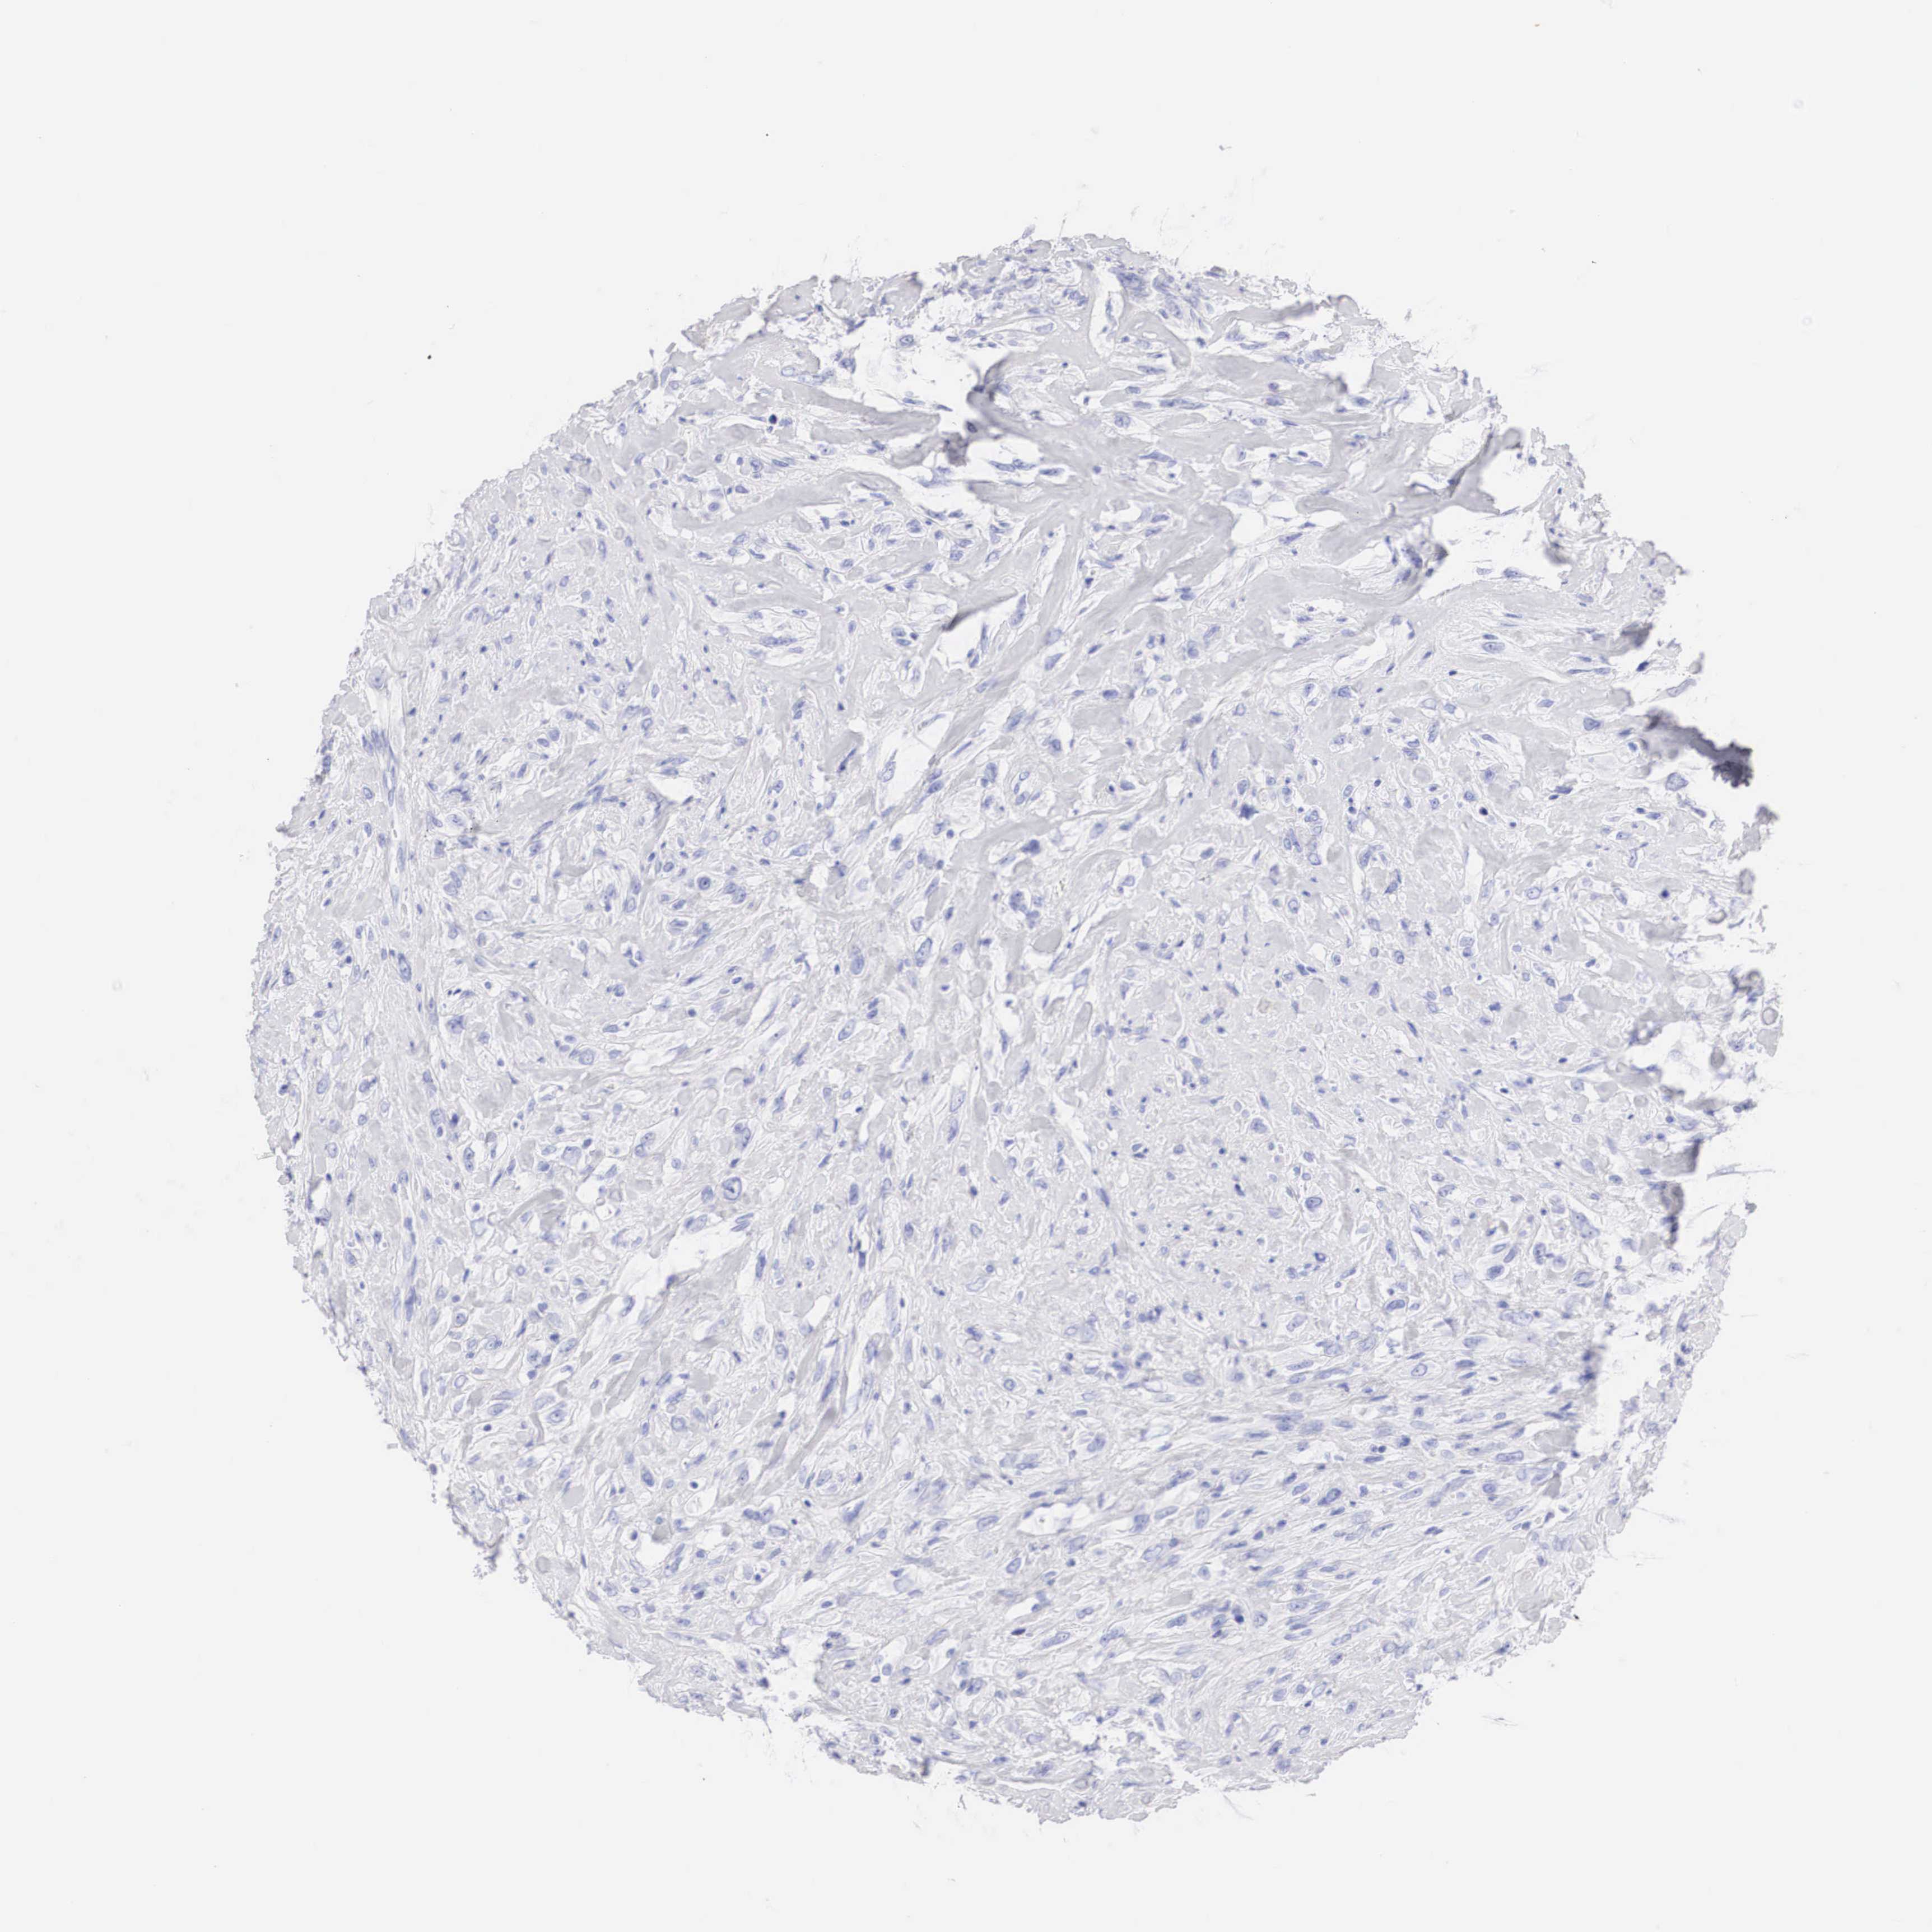

BRCA TCGA BRCA VALIDATION PROTEIN EXPRESSION

ANTIBODIES

AND

VALIDATION